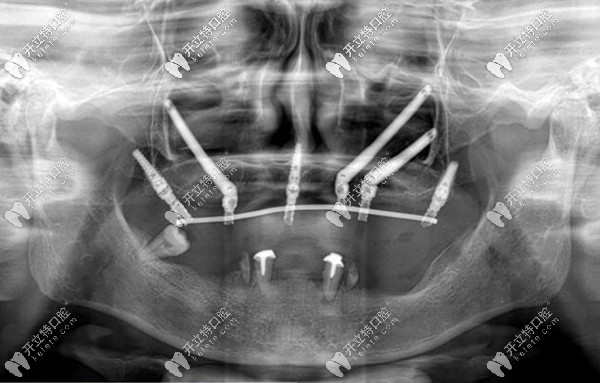

關(guān)于穿顴骨穿翼板種植牙要多少錢,參考價(jià)格看完便知

修改時(shí)間:2025-05-04

關(guān)于穿顴骨穿翼板種植牙的收費(fèi)價(jià)格,以及優(yōu)缺點(diǎn),文中都有介紹哦。